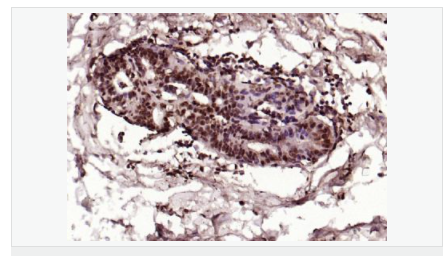

產品應用ELISA=1:5000-10000 IHC-P=1:100-500 IHC-F=1:100-500 Flow-Cyt=1μg/Test ICC=1:100 IF=1:100-500 (石蠟切片需做抗原修復)